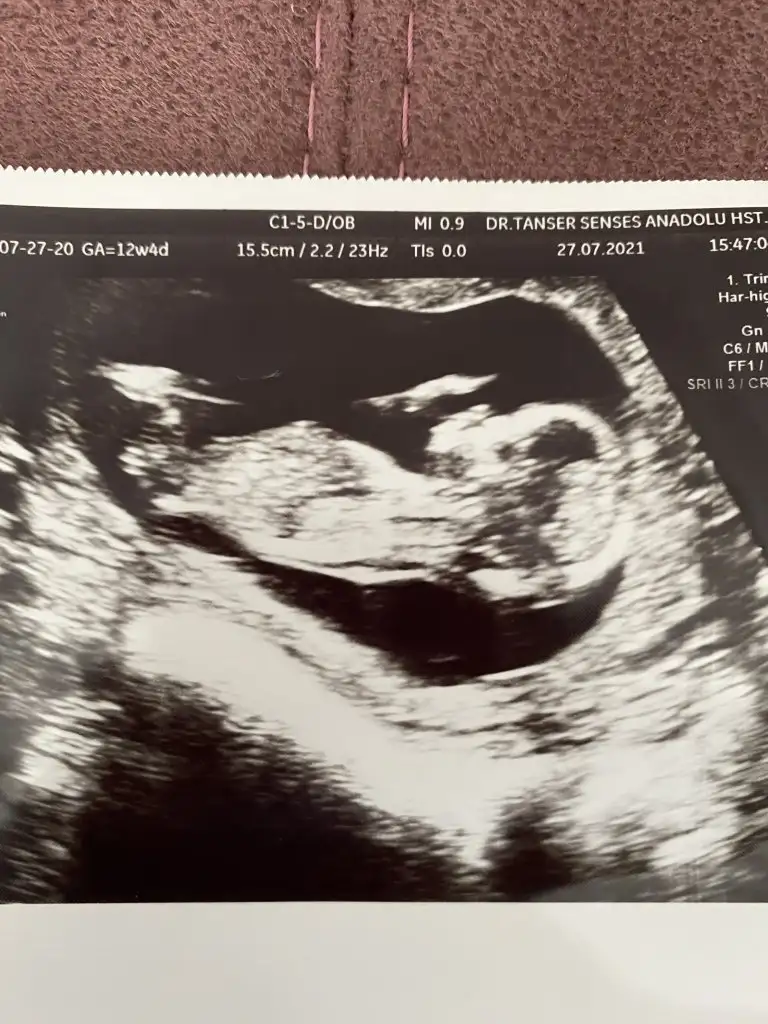

12+6 haftalık hamileyim cinsiyet tahmininiz nedir ?Erkek görünüyor![]()

Sırtı dönmüş12+6 haftalık hamileyim cinsiyet tahmininiz nedir ?![]()